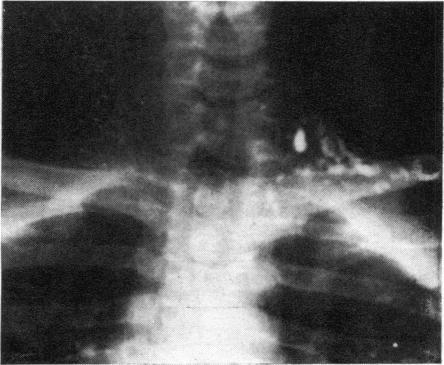

The changes in the thoracic duct were studied in schistosomatic hepatic fibrosis, particularly in cases with ascites. The postmortem findings, lymphangiography, and clinical thoracic duct cannulation showed that, particularly in cases with ascites, the thoracic duct is dilated, pressure within is raised, and the lymph flow is increased. The significance of these findings is discussed in relation to the site and the treatment of ascites.